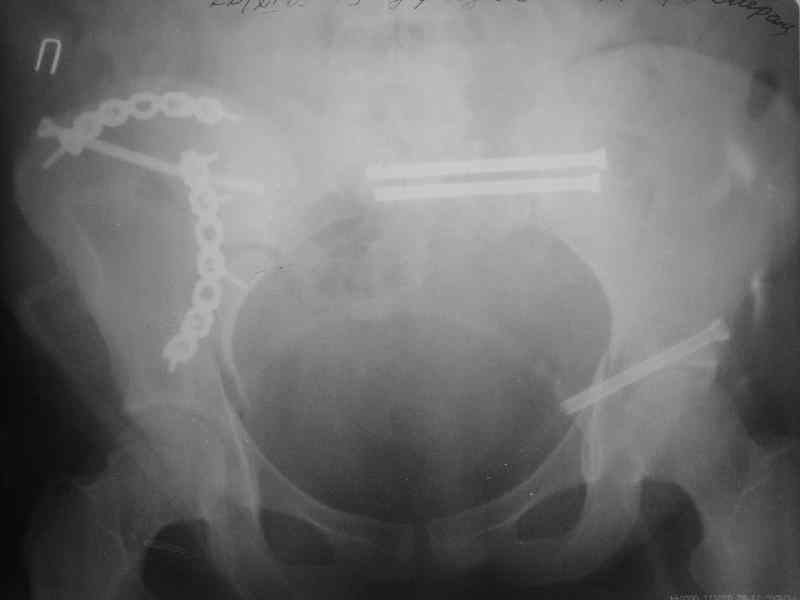

Здравствуйте, коллеги. Какие будут мнения по поводу лечения представляемой больной?

Молодая девушка 19 лет, травма 1 год назад, тогда же прооперирована.

В настоящее время имеются ноющие боли в области крестца слева, нарушение походки, ощущение неуверенности, слабости в левой нижней конечности, неврологически -непостоянные парестезии в левой нижней конечности. Ходит с дополнительной опорой, страдает от ожирения.

Какова по вашему будет оптимальная тактика в отношении несращения крестца? Замена винтов на более длинные с коррекцией их положения+ туннелизация зоны нестращения, открытое вмешательство с костной аутопластикой или еще какие варианты?

В приложении снимки при поступлении и послеоперационные год назад.

Могу сказать одно: миграция винтов и нестабильность синтеза левого подвздошно-крестцовогоо сочленения очевидна.